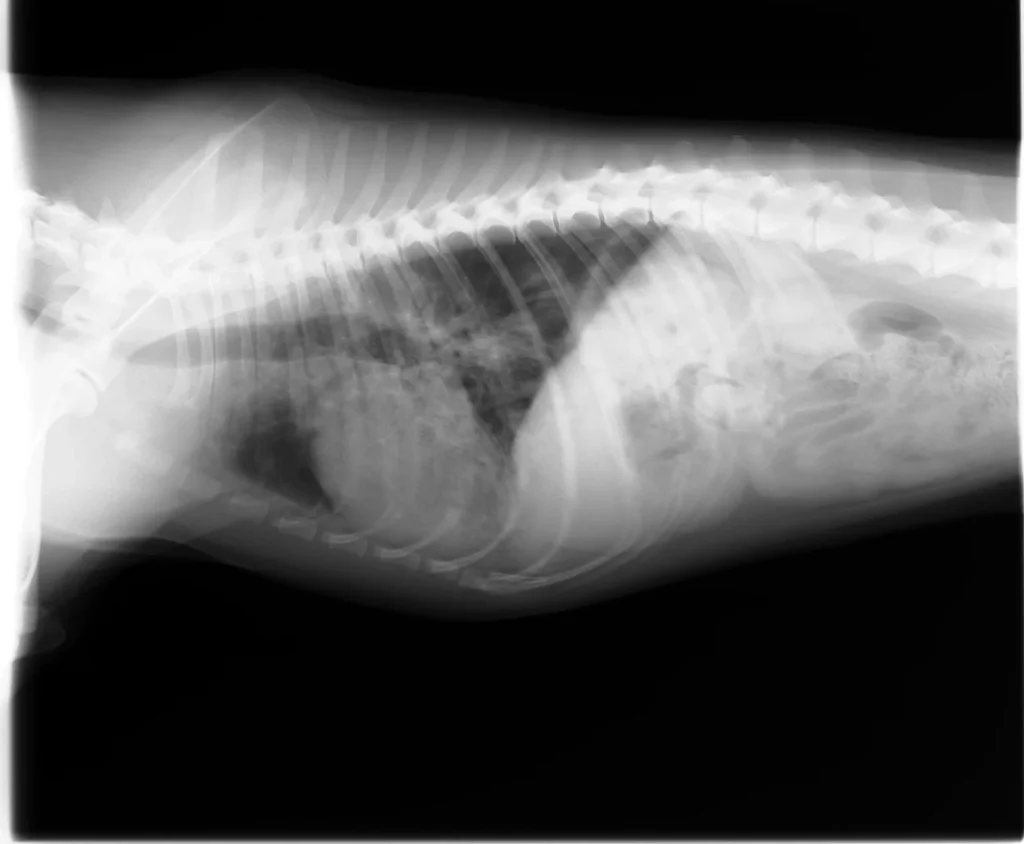

当院ではこのような呼吸器疾患のワンちゃんネコちゃんにおいて、血液検査、レントゲン検査に加え、気管支鏡などの検査も実施しております。ただ、気管支鏡は麻酔をかけての検査になります。そのため麻酔をかけないでできる検査までで、まずは全体を把握させていただきたいと考えております。